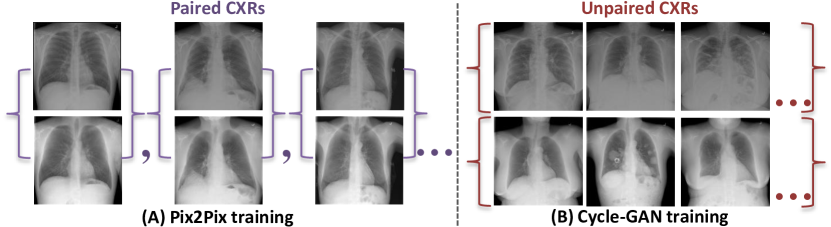

Dual-energy subtraction imaging captures two or three radiographs of the same patient with different energy levels of X-ray exposures. One of the captured images highlights only the bones based on a specific energy level. Thus, the suppressed bone image can be estimated by combining the acquired standard chest X-ray image which includes both the soft tissue and bones and bone-only image. Therefore, we are motivated to utilize image-to-image translation techniques to translate a standard radiograph into a soft tissue only radiograph, thereby suppressing the bone structures. In this work, we adopt paired and unpaired training to accomplish this task (See Figure 1).

Refer to caption

Figure 1: (A) Paired training radiographs consist of training pairs where the correspondence within each radiograph pair exist. (B) Unpaired training radiographs consist of a source set and a target set, with no information provided as to which standard CXR matches which bone suppressed CXR. Top row: standard chest radiographs. Bottom row: bone suppressed chest radiographs using the dual-energy technique.